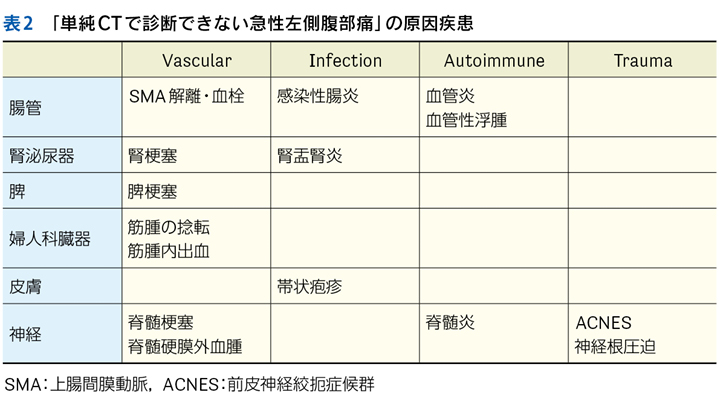

▶ 最後に,SQについて大切な点を補足しておく。それは「〇〇がない」という陰性情報も重要なSQとなりうる,ということだ。診断に関連する(鑑別に挙がっている疾患の確率を上げ下げする)陰性情報をpertinent negativesと言うが,これは時に陽性情報(「〇〇がある」)と同等,あるいはそれ以上に重要となることがある。「突然発症した腹膜刺激徴候のない重度の腹痛」「局所症状のない遷延性発熱」「単純CTで尿路結石がみられない突然の片側側腹部痛」のように,意味のある陰性情報をSQとして用いることで鑑別のフレームをぐっと狭めることができる。SQによる修飾の際には,こういったpertinent negativesも意識しておきたい。